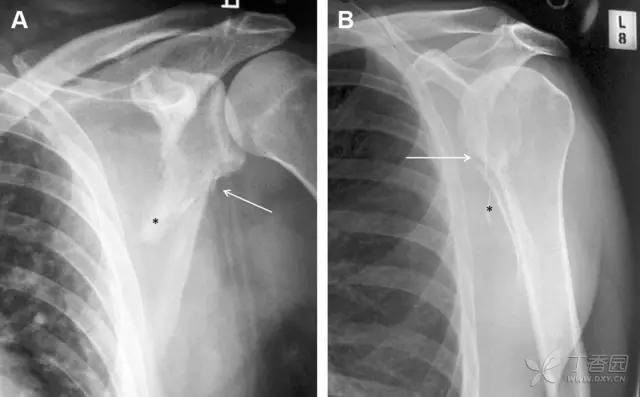

图 3 肩胛骨骨折正侧位片:由于骨块的叠加,(A)前后位片示「V」形高密度影(*),肩胛颈下方可见骨皮质碎片(箭头);(B)侧位片示骨皮质中断,骨折段移位,但由于肱骨的重叠遮挡,决断往往比较困难